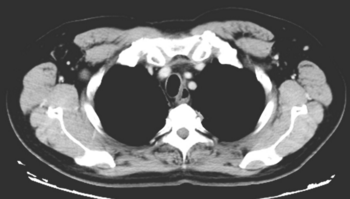

1小时条评论15岁女性患者,无明显诱因左上肢持续性隐痛起病,无其他放射痛,局部软组织肿胀,无发热、红肿。症状持续存在,未予治疗。两个多月后,胸腹部CT示:两肺多发结节影。 基本情况 【病史摘要】 患者,女,15岁,身高150cm,体重53kg,体表面积1.43m2。2010年11月...